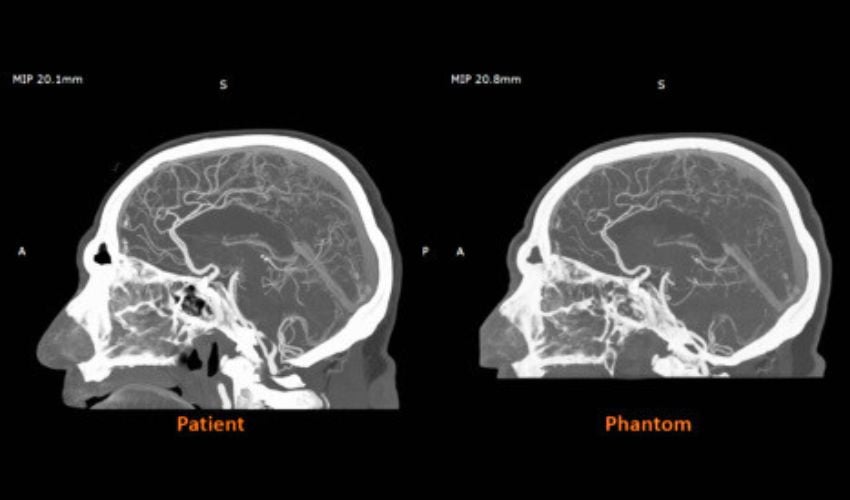

A key advantage of the material is the ability to tune Hounsfield unit values. This tuning allows printed structures to mimic bone, gray matter, fat, veins, or any feature expected in a clinical scan. Early work between Stratasys and Siemens Healthineers shows that RadioMatrix phantoms can match human tissue densities with deviations as small as a single Hounsfield unit (HU). This level of precision is nearly indistinguishable from real tissue on a CT scan and supports the accurate replication of complex anatomy. This accuracy makes the material well suited for imaging education, the study of pathology, and the validation of CT protocols and imaging algorithms.

In the United Kingdom, partners such as Beaumont Hospital and CPI have already used the material to produce cerebral angiography models for training in imaging guided procedures. These early results show that printed radiopaque anatomy can support more consistent and controlled training environments. The material also benefits manufacturers and researchers who need reliable test models for new devices and imaging tools. Instead of waiting for donor material or relying on generic phantoms, teams can print standardized structures tailored to their studies. With expanded access now in place, more U.S. institutions are expected to adopt radiopaque 3D printing and deepen their use of Digital Anatomy technology. To learn more about the RadioMatrix™ materials, click HERE.